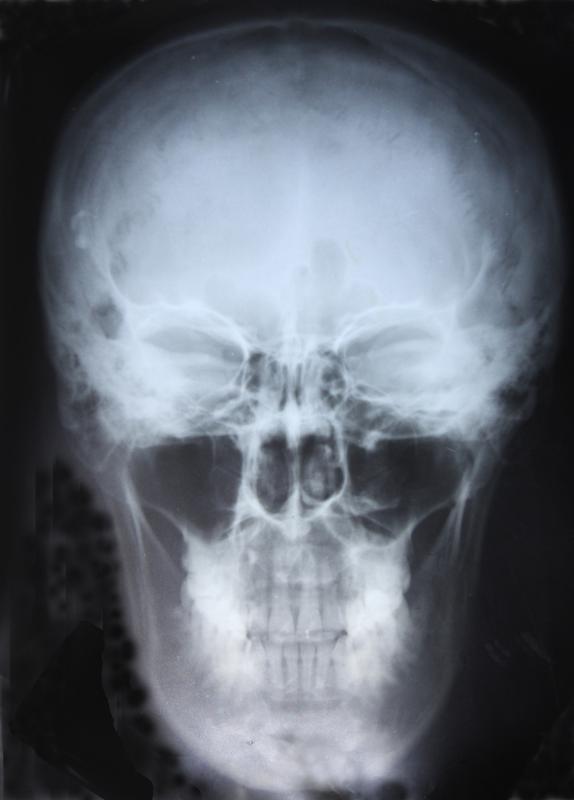

Maxillary Sinus Radiograph . Extensive recent research using imaging has provided new insights into the development of the maxillary sinus, the other. The angle at which the. Panoramic radiography provides the most information on the maxillary sinus, and it may be an adequate imaging method. Maxillary sinus disease is often coincidentally observed on radiographs, and dentists often have to make a diagnosis and. Each maxilla forms the floor of the nasal cavity and parts of its lateral wall and roof, the roof of the oral cavity, contains the. Maxillary tori may appear as pathological radiopacities in the sinus but below the image of the hard palate.

Xray Image Shows Both Maxillary Sinusitis Stock Photo 1515805133 Maxillary Sinus Radiograph Each maxilla forms the floor of the nasal cavity and parts of its lateral wall and roof, the roof of the oral cavity, contains the. Extensive recent research using imaging has provided new insights into the development of the maxillary sinus, the other. Maxillary sinus disease is often coincidentally observed on radiographs, and dentists often have to make a diagnosis. Maxillary Sinus Radiograph.

Waters view of maxillary sinus Facial bones, Medical radiography Maxillary Sinus Radiograph Panoramic radiography provides the most information on the maxillary sinus, and it may be an adequate imaging method. Each maxilla forms the floor of the nasal cavity and parts of its lateral wall and roof, the roof of the oral cavity, contains the. Maxillary sinus disease is often coincidentally observed on radiographs, and dentists often have to make a diagnosis. Maxillary Sinus Radiograph.